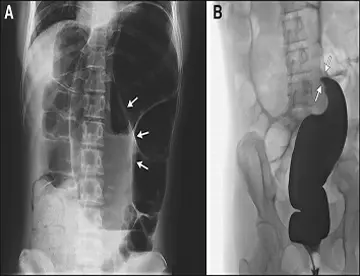

بلع اسباب‌بازی

یک خانم 72 ساله با سابقه‌ی 3‌روزه‌ی درد دور ناف به بخش اورژانس مراجعه کرد. او قبلاً یک باراستفراغ کرده بود.

دانه قهوه و نوک پرنده